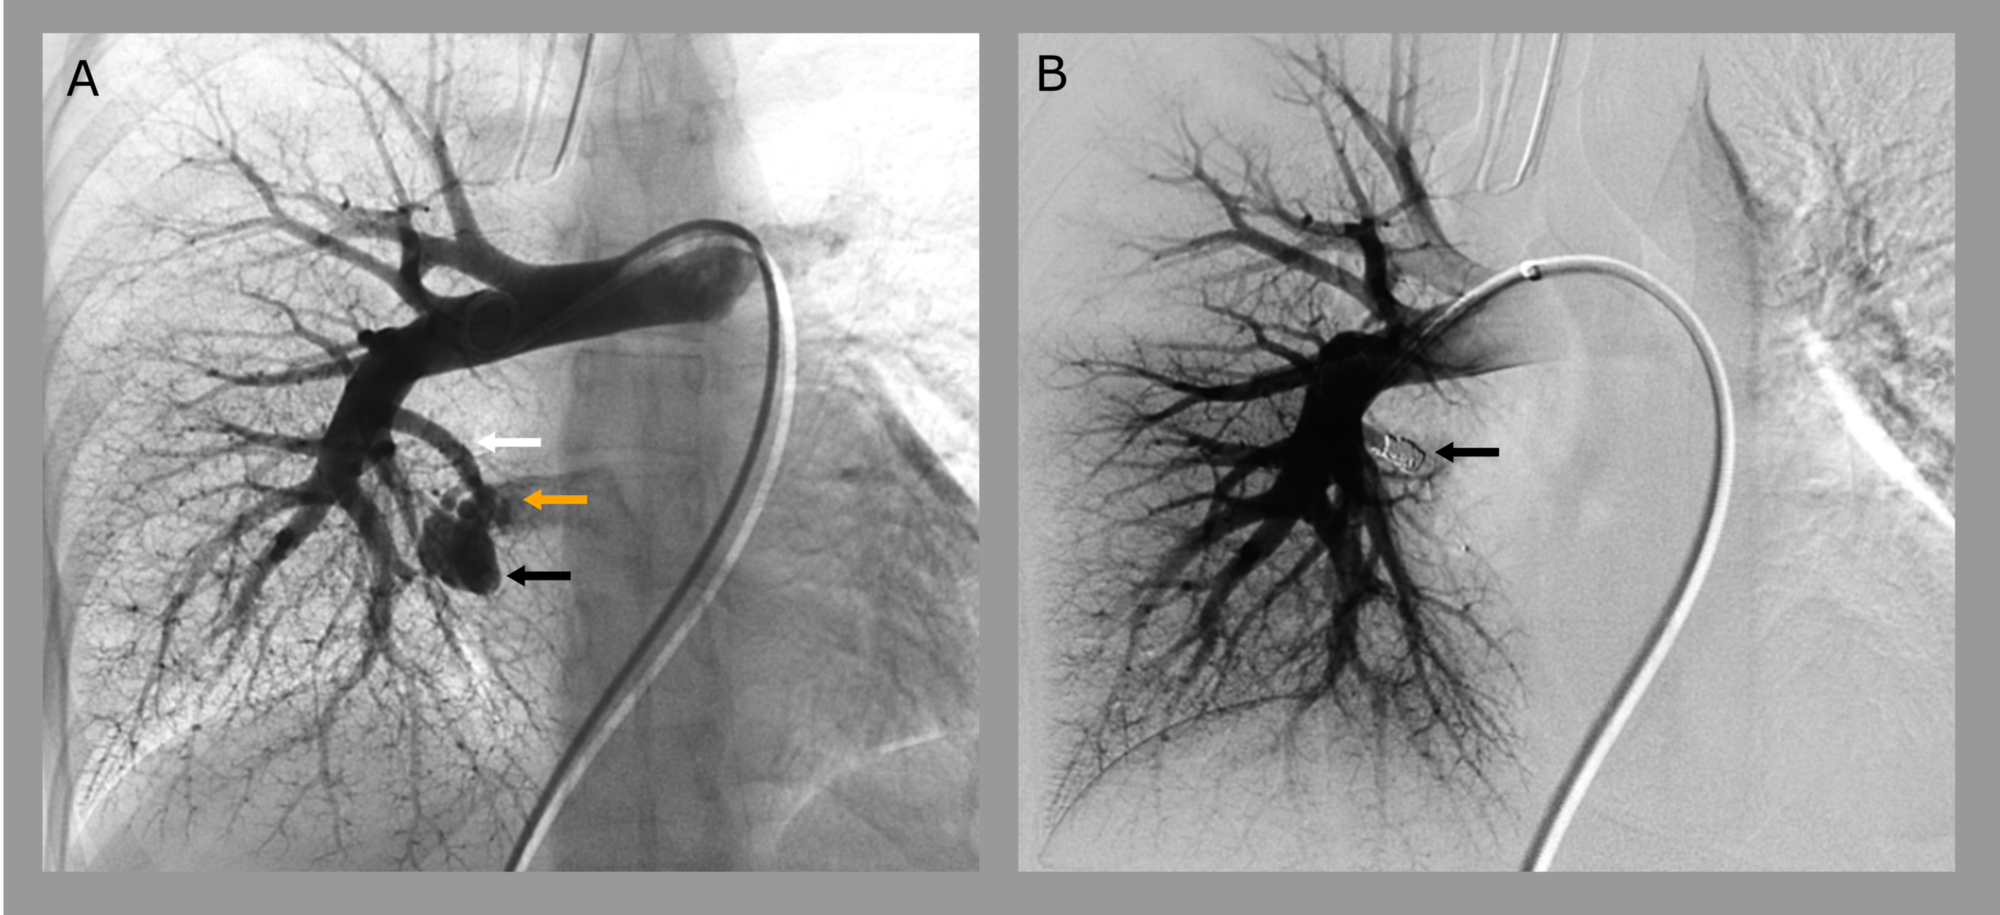

Cureus Pulmonary Arteriovenous Malformations A Rare Cause of Coil Embolization After Stroke Coil embolization is an interventional procedure that is less invasive than clipping and can be done while the patient is. An aneurysm coil is a device inserted via catheter to fill in a brain aneurysm — a bulge in a blood vessel. Transient global amnesia following coil embolization for a basilar. Sentinel headaches come on suddenly and may sometimes be. Coil Embolization After Stroke.